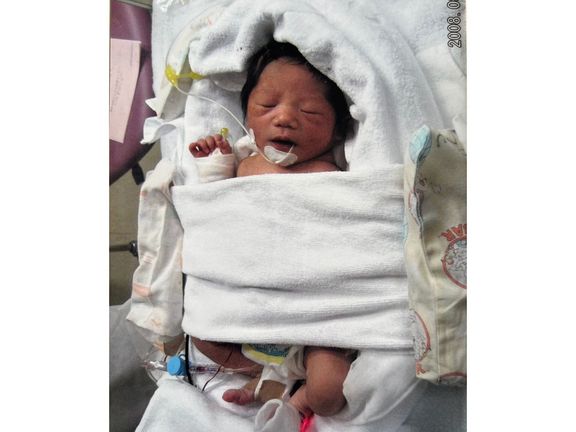

妊娠23週で604gと552gで生まれた双子。壊死性腸炎を発症した弟は、3回の手術をするも生後60日で空へ【多胎・低出生体重児】赤ちゃん・育児

妊娠23週で604gと552gで生まれた双子。壊死性腸炎を発症した弟は、3回の手術をするも生後60日で空へ【多胎・低出生体重児】赤ちゃん・育児 -